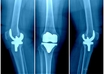

'Knee implant price cut boon for people but ensure quality does not go down'